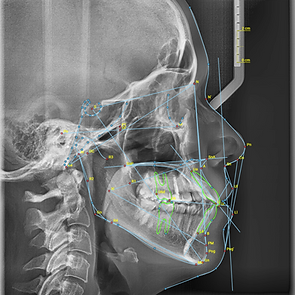

Ceph Assistant is an advanced online software designed to help orthodontists perform quick and precise dental analyses. It offers versatile options, including profile photo analysis, frontal photo analysis and cephalometric analyses. Choose from several popular cephalometric analysis types, such as Ricketts, Steiner, McNamara, Hasund, Eastman, and ABO, or customize your own analysis to include the parameters that best meet your needs. The cephalometric analysis report includes the analyzed image, a comprehensive result table, insights into facial growth patterns and the harmony box.

Cephalometric analysis

10+ standard analysis types

Artificial intelligence analysis support

Cephalometric analysis types